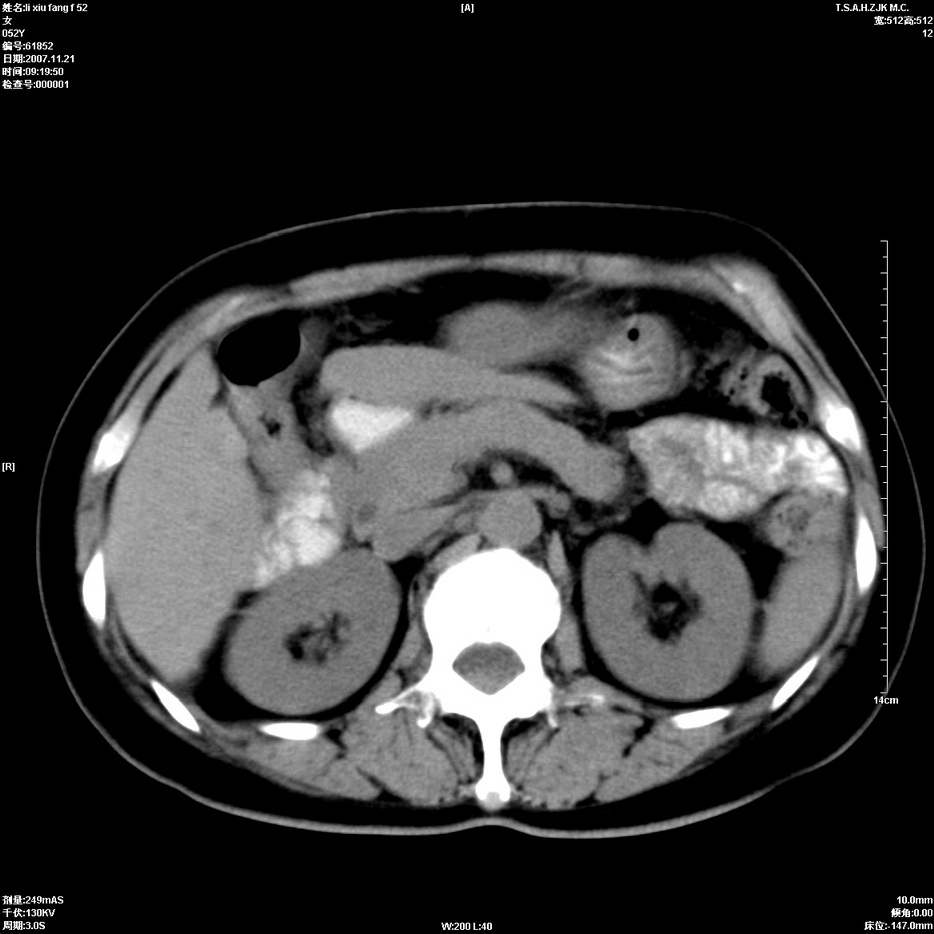

标题: CT12858:女,52岁,胎甲球蛋白861肝左叶占位,肝癌。下腔静 [打印本页]

标题: CT12858:女,52岁,胎甲球蛋白861肝左叶占位,肝癌。下腔静

肝左叶巨大低密度灶肿块,增强符合快进快出表现,有动静脉交通支;静脉期,下腔静脉内有充盈缺损,afp明显升高,支持肝癌并下腔静脉癌栓形成。

支持楼主   门静脉主干及左支癌栓形成

以下是引用拾荒者在2008-4-15 22:57:00的发言:[br]肝左叶巨大低密度灶肿块,增强符合快进快出表现,有动静脉交通支;静脉期,下腔静脉内有充盈缺损,afp明显升高,支持肝癌并下腔静脉癌栓形成。